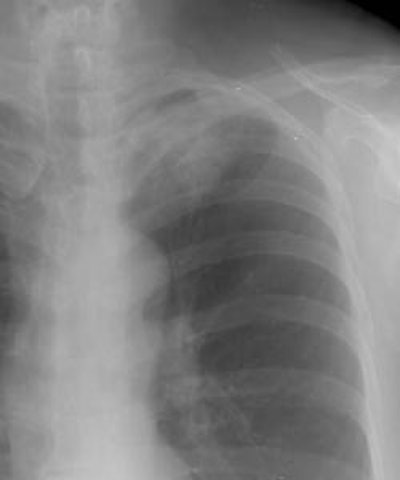

Example 1: In this case the patient had a large left upper lobe adenocarcinoma which was abutting the pleural surface on CT (Click here to view the patients CT scan). During percutaneous biopsy of the lesion, the patient developed a pneumothorax (white arrows) and the lesion could be seen to fall away from the lung apex indicating that there was no chest wall invasion. Although not intentional, a post-procedure pneumothorax can sometimes provide useful information.

08290111235796 Ptx And Lesion Moves Cxr S